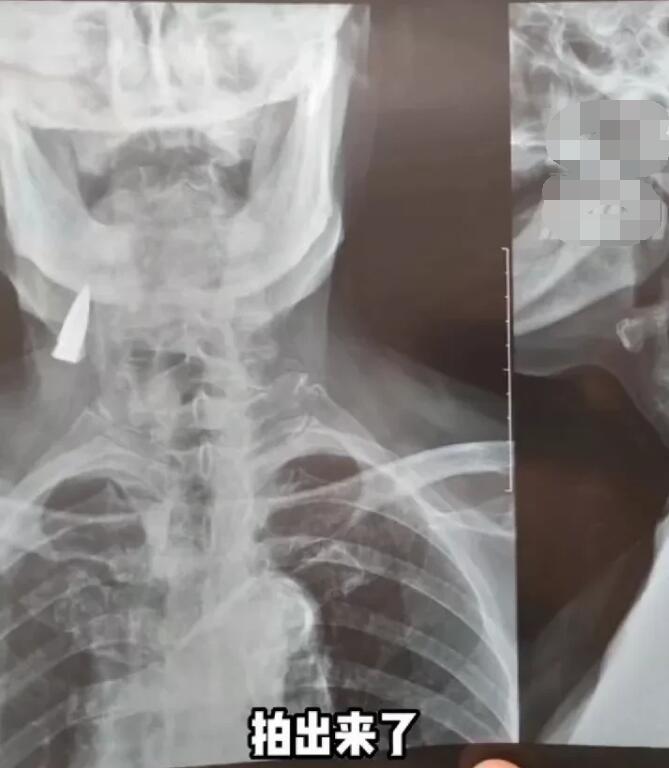

95岁抗日老兵拍片发现颈部有子弹,无数先烈换来了和平,致敬英雄

近日,在山东临沂,一位95岁的抗战老兵拍片时,发现颈部遗留有一颗子弹头,起因是老人摔了一跤,去拍片,拍出来了!就在老人颈部右侧,抗日时期让日本鬼子包围了他们,过河撤退的时候他背着一个伤员受的伤。他们一个排54个人只剩了6个人!可是那个时候受的伤,身体别的地方也有弹片!老人的女婿表示以前就知道有弹片,不知道在哪个位置,老人这么一说,结果在颈部就被发现了!

当时检查出来后,感觉很震惊,我们觉得幸福来之不易!最后拿到光片后,老人子女都惊呆了,原来是一个子弹头,在父亲体内残留了几十年。家里人考虑到老人的年龄,就没有动手术,按照医生的说法保守治疗,以减少身体不适在这里我们也致敬这位老兵,因为有他们的抛头颅洒热血,才有了我们现在的幸福生活!

我相信历史会始终铭记他们为祖国做出的贡献,他们的精神将永垂不朽!我想这颗陪伴老人半辈子的子弹也是他在战场上荣誉的象征,更是那段峥嵘历史的见证!在此,我们向所有的老兵致敬,愿他们能够安享晚年,有一个美好的夕阳岁月,辛苦了一辈子,呕心沥血付出了太多,英雄迟暮,也该有个安定的晚年了!